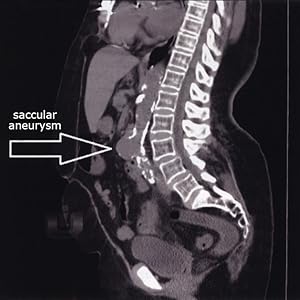

The new second edition of Inside Ultrasound's Vascular Reference Guide has updated and additional protocols to help document more conditions that affect vascular patients. The Principles of Interpretation and Diagnostic Criteria sections in each testing chapter have been reorganized into an easy-to-follow format. New chapters in this edition include pelvic anatomy, ergonomics and a quick reference chapter summarizing key measurements and calculations. Chapters have been enhanced with even MORE images and cine clips! This book is the essential reference guide for all students, educators, technologists, sonographers and physicians.

Each section contains: topic definitions, principles, etiology of disease, risk factors, indications, contraindications, mechanism of disease, location of disease, patient history, physical exam, exam protocols, interpretation, differential diagnosis, correlation and medical, surgical and interventional treatments, as well as "protocol at a glance" sections, for easy test referencing.

Chapters include: fluid dynamics, vascular disease, anatomy, physiology, testing and optimization, measurements & calculations, worksheets, interpretation, report examples, extensive references, pharmacology, Comprehensive Chapter on the Cardiac Effects on Spectral Doppler, a Glossary and more...

Visual Features: Full color images, anatomical drawings, quick reference tables and tips throughout the book,

396 pages with more than 1,200 images, 150 tables, 110 cine clips and detailed information on: